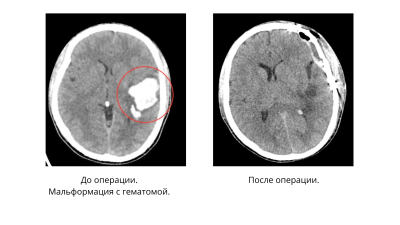

Заведующая отделением Наталия Бурда рассказала, что при проведении компьютерной томографии у пациента обнаружили внутримозговую гематому в левой височно-теменной области. Медлить было нельзя.

Нейрохирурги во главе с Ревазом Джинджихадзе провели костно-пластическую трепанацию черепа и удалили гематому с применением микрохирургической техники.

Операция прошла успешно. Пациент трое суток находился на лечении в отделении реанимации, а затем его перевели в отделение нейрохирургии. Сейчас молодой человек дома. У него прошли головные боли, нормализовалось давление и практически полностью восстановилась речь.